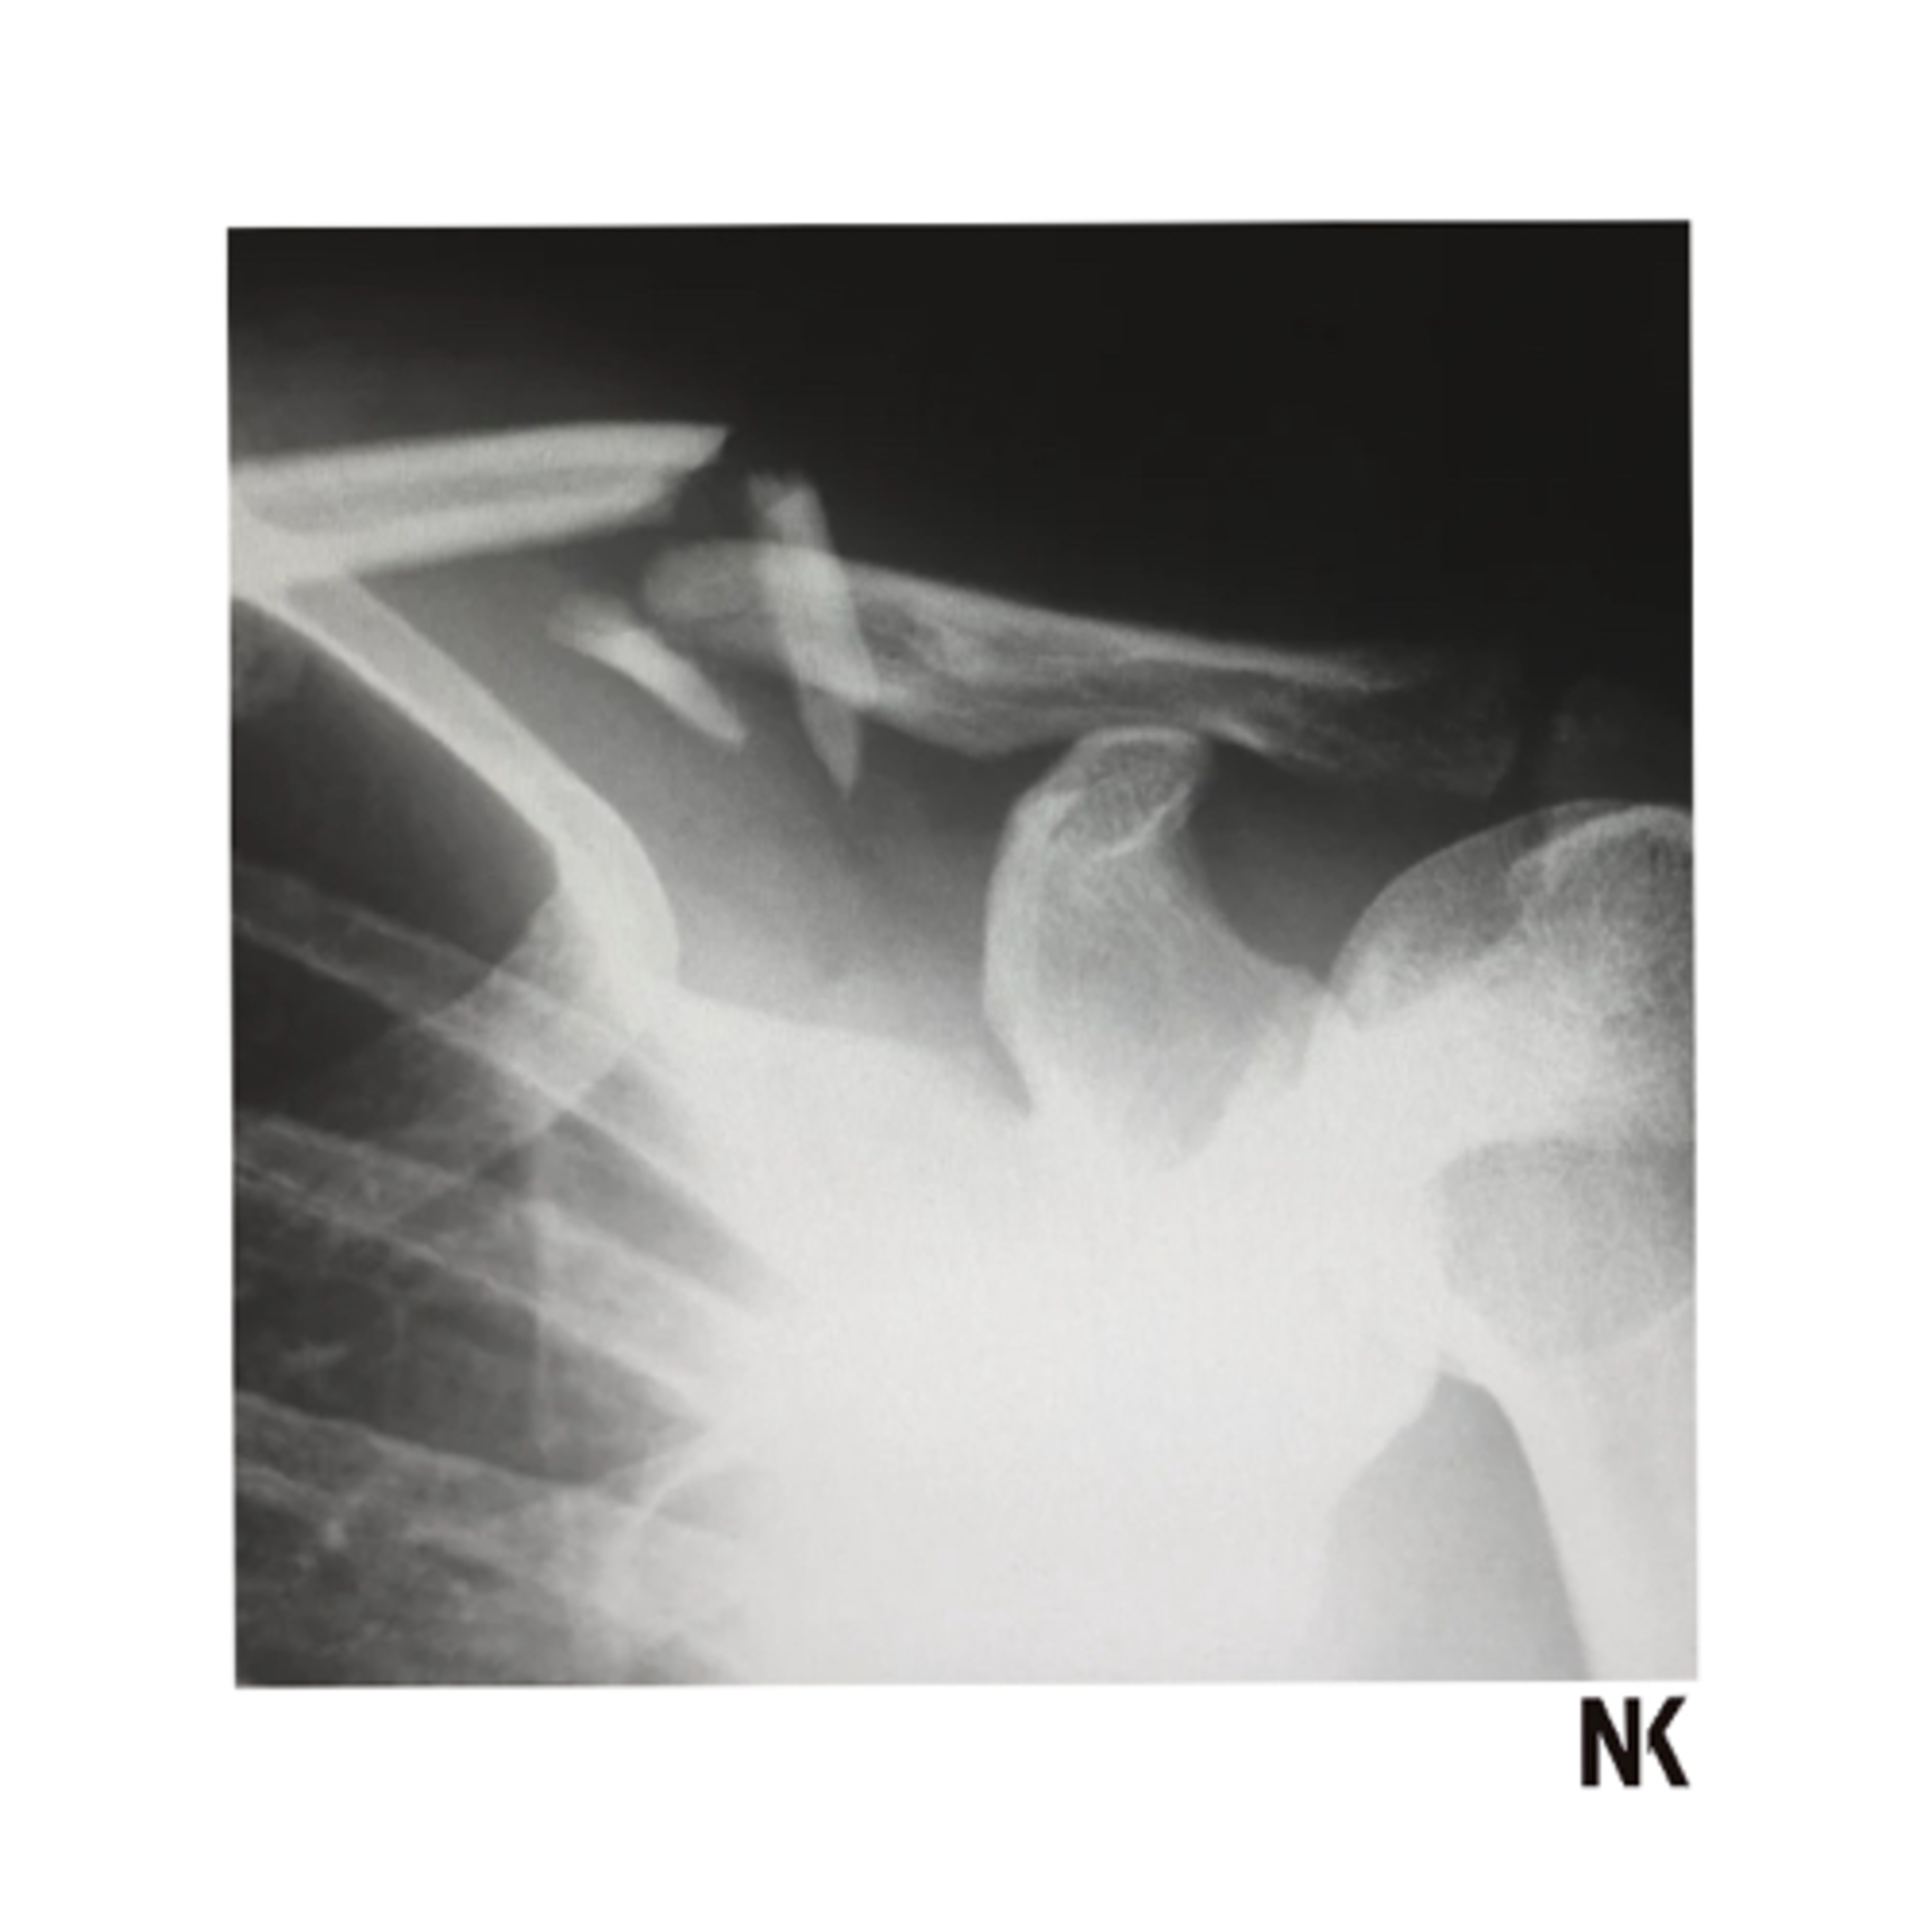

If fractures aren’t fixed, they tend to spread into a much bigger break! God wants to fix the fracture at the source. Fractures start in the heart and end up affecting relationships, and every area of your life.